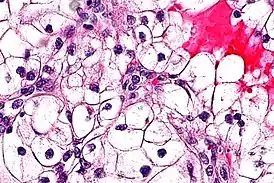

![]() Типичная гистологическая картина светлоклеточного рака почки в высоком разрешении. Окраска гематоксилином и эозином. | |

Клетки светлоклеточного рака почки обычно имеют светлую, прозрачную цитоплазму, хорошо различимую клеточную мембрану, и содержат шарообразное, более или менее обычно выглядящее, ядро[2].

Консенсусом экспертов ВОЗ предложена следующая градация степени злокачественности светлоклеточного рака почки по микроскопически наблюдаемой гистологической картине[2]:

- 1-я степень: Клетки опухоли имеют базофильное и, в целом, не выглядящее сколь-нибудь подозрительным, ядрышко, которое с трудом различимо при увеличении в 400 раз;

- 2-я степень: Клетки опухоли имеют очерченное, хорошо различимое при увеличении в 400 раз ядрышко с эозинофильной, а не с базофильной окраской;

- 3-я степень: Клетки опухоли имеют очерченное и более крупное, чем в первых двух случаях, ядрышко, которое хорошо различимо уже при увеличении не в 400, а всего в 100 раз;

- 4-я степень: Клетки опухоли проявляют высокую или очень высокую (исключительную) степень плеоморфизма (то есть морфологически мало похожи одна на другую, имеют необычно большие различия строения и внешнего вида), выглядят низкодифференцированными, или же имеют рабдоидную либо саркоидную морфологию.